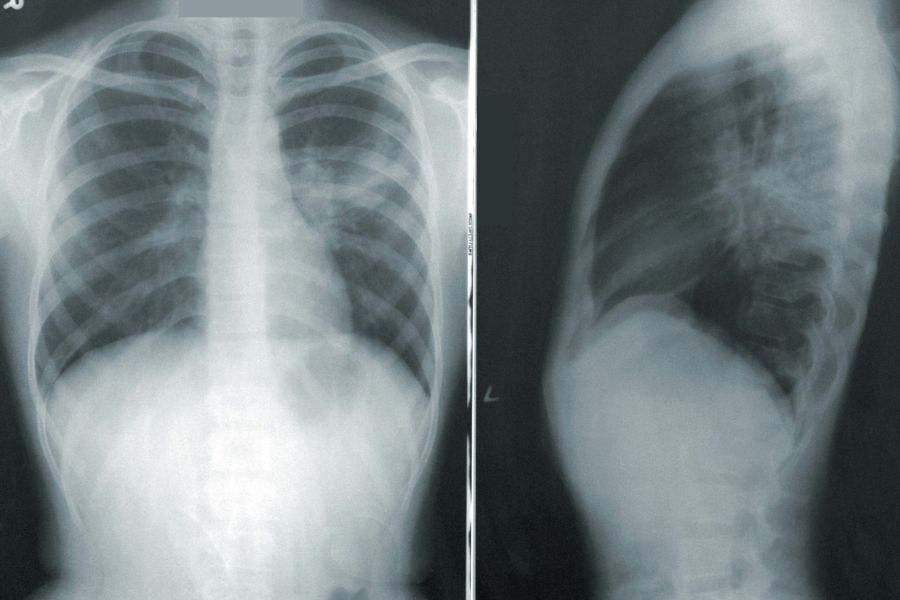

AI helpt bij longkankerscreening: veertig procent minder vals-positieve uitslagen

september 17, 2025

Grote stap vooruit voor longkankerscreening dankzij AI Onderzoekers van het Radboudumc hebben AI ontwikkeld die het aantal vals-positieve uitslagen van longkankerscreening met veertig procent vermindert. Vals-positieve uitslagen leiden tot onnodige vervolgscans, extra kosten en angst bij patiënten. ‘We zijn overtuigd van de baten van longkankerscreening, maar de lasten moeten we terugdringen. Dit is een grote […]